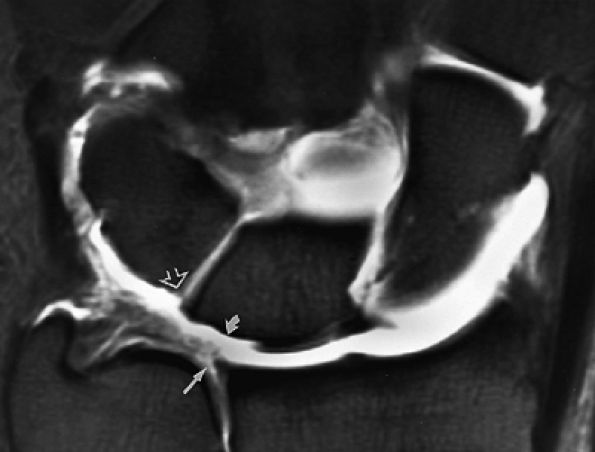

FIGURE 10.63 ● The long radiolunate or radiolunotriquetral (RLT) ligament. (A) The RLT ligament is divided into a radiolunate ligament and lunotriquetral component. The RLT ligament functions as a volar sling for the lunate. L, lunate; R, radius. Volar FS coronal T1-weighted arthrogram. FS axial T1-weighted arthrograms obtained at the level of the proximal (B) and distal (C) aspects of the radial styloid show the volar course of the RLT ligament (large arrows) from the radial styloid (R) inserting into the lunate (L) and blending with the volar portion of the lunotriquetral interosseus ligament. The lunate attachment of the scapholunate interosseous ligament volar fibers is deep to the lunate attachment of the RLT ligament (B). S, scaphoid; T, triquetrum; SL, scapholunate ligament.